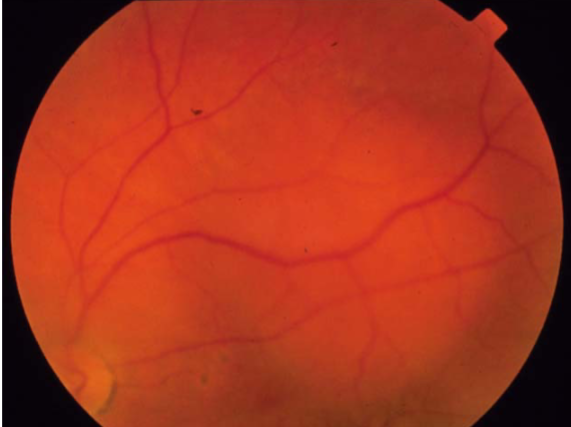

low

what is the concern for this being melanoma?

low

what is the concern for this being melanoma?

low

what is the concern for this being melanoma?

low

what is the concern for this being melanoma?